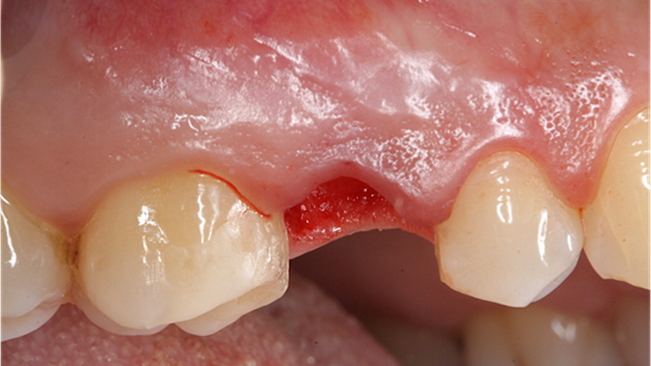

Clinical case: AnyRidge immediate loading

- Courtesy of Dr. Andres Paraud Freixas, Chile -

Keywords

AnyRidge, ISQ value, initial stability, immediate loading, KnifeThread, maxillary anterior, Mega ISQ, Dr. Andres Paraud Freixas

“Patient’s smile was recovered on the day of surgery

with reliable & highly-aesthetic results using AnyRidge & R2GATE. ”